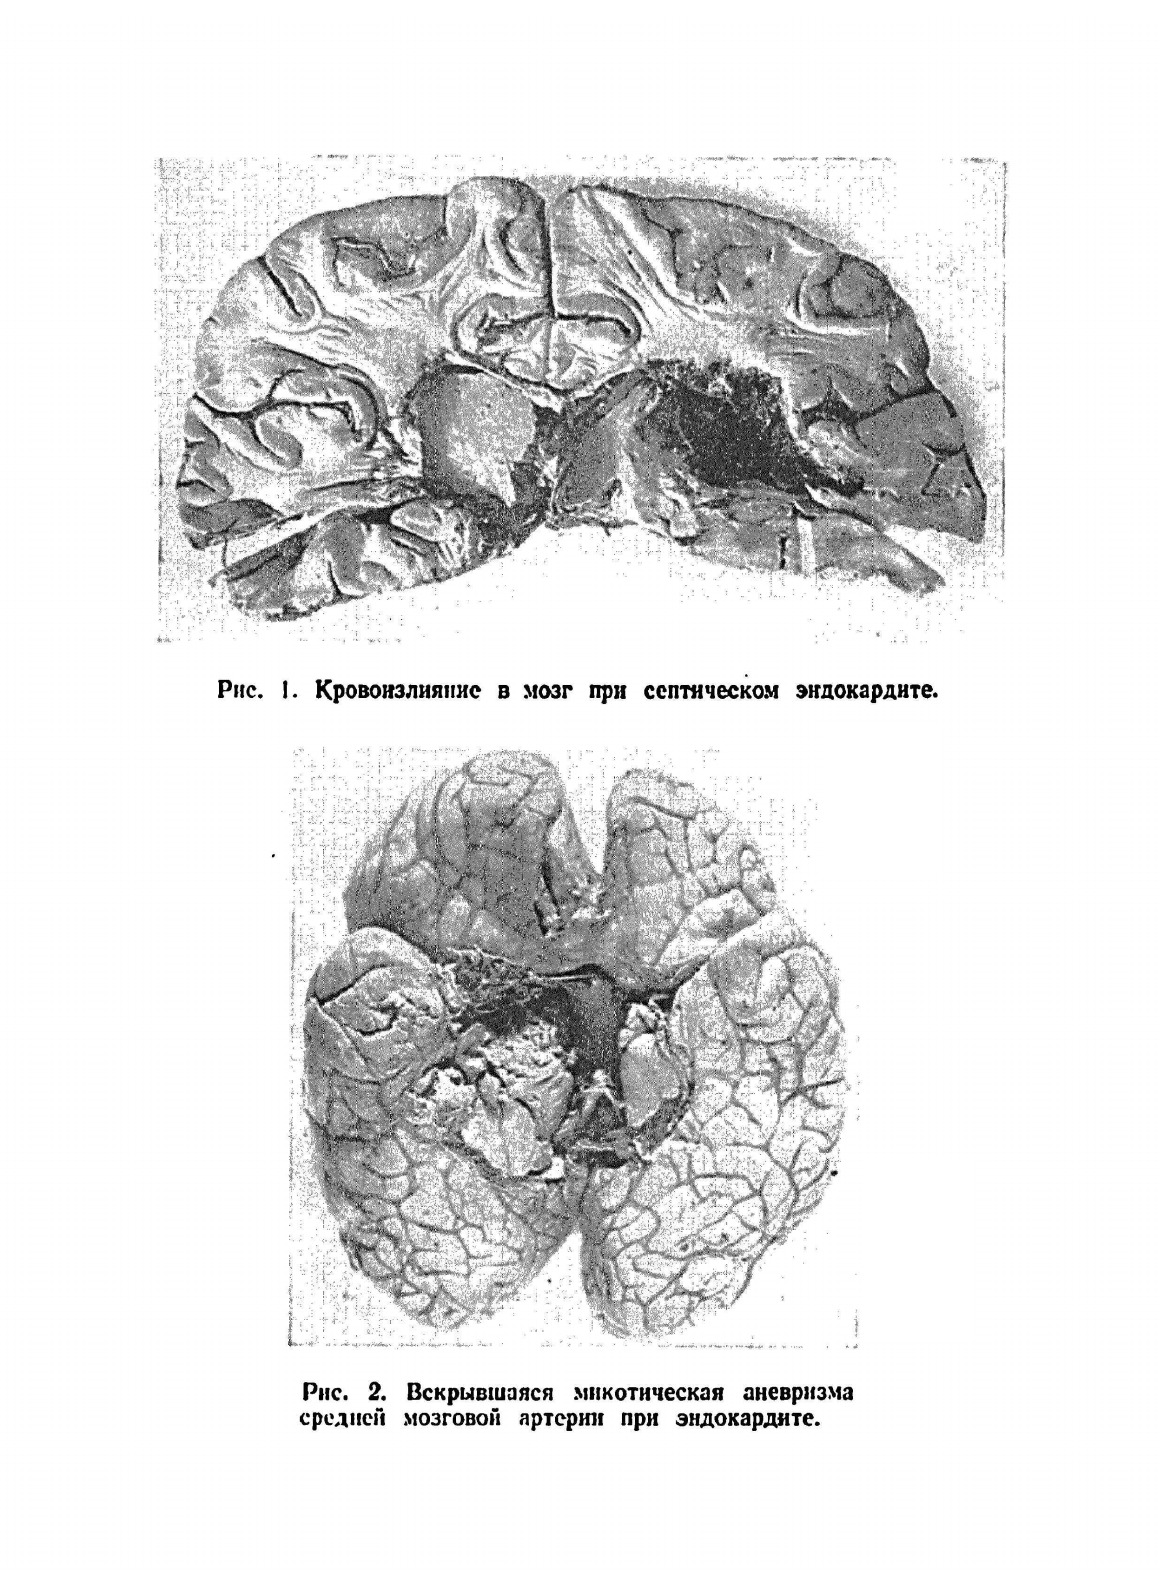

Книга рассчитана не только на невропатологов и терапевтов, но представляет интерес для широкого круга врачей общего профиля. Описана клиника, патологическая анатомия и патогенез поражений нервной системы при внутренних болезнях. Освещены также вопросы лечения этих болезней. Особое внимание уделено невропатологическим синдромам, наблюдаемых при болезнях сердечно-сосудистой системы, крови и кроветворных органов, легких, печени, и болезнях обмена.